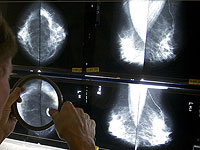

Донор спермы с генной мутацией, радикально повышающей риск развития рака, стал отцом 200 детей по всей Европе. Это выяснилось в ходе масштабного расследования, проведенного крупными вещателями, включая CBS News, BBC News.